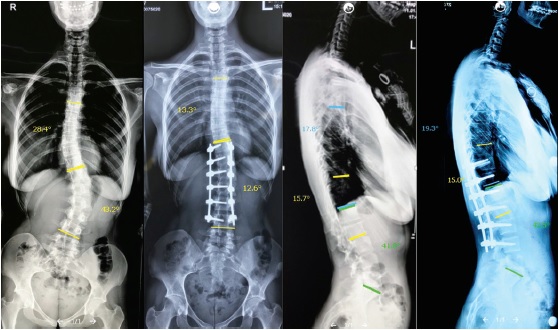

The first group included 54 patients with lumbar or thoracolumbar idiopathic scoliosis aged 16 to 41 years: 48 women and 6 men. Classic posterior correction with the use of transpedicular screws was performed in this group. Posterior approach with stripping of the posterior vertebral elements was performed, transpedicular screws were inserted using the free-hand method with subsequent X-ray examination, and posterior release (Ponte osteotomy at several levels) was carried out in some patients. Three-plane correction using rods and posterior spine fusion were performed (Fig. 1).

Fig. 1. X-rays of a 31-year-old patient with left-sided lumbar scoliosis before and 2 years after posterior correction and T11-L4 fixation. Satisfactory result was achieved. No loss of correction was observed at the long-term follow-up